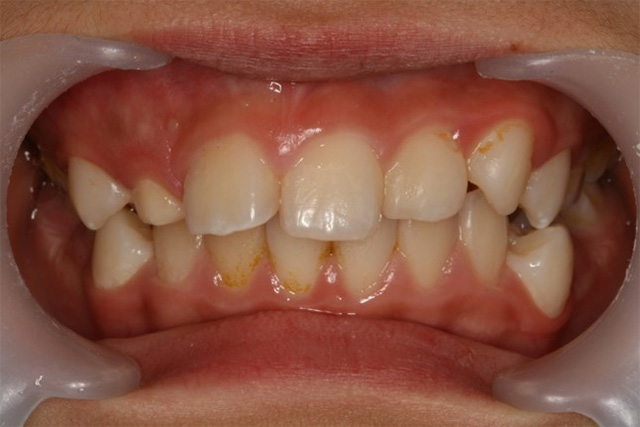

매복치로 인해 치열이 틀어진 모습/사진=일산병원

이가 정상적으로 나오지 못하고 잇몸이나 턱뼈 안에 남아 있을 수 잇다. 이것이 '매복치'다. 이가 나올 공간이 부족하거나 유치(乳齒)가 제대로 빠지지 못하는 등의 원인으로 발생한다. 매복치는 보통 10~11살에 많이 발견되는데 치료 시기를 놓치면 주변 다른 치아 뿌리를 녹이거나 전체 치열을 틀어지게 할 수 있다. 국민건강보험 일산병원 치과교정과 이지연 교수는 "매복치 주변으로 물혹이 생기기도 해 성장기 어린이는 정기적인 구강검진으로 조기 발견해 옆 치아를 빼야 하는 상황이 생기지 않도록 해야 한다"고 말했다.